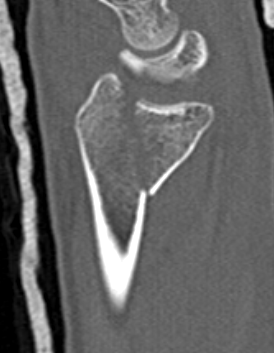

Distal radius fracture with shortening and dorsal tilt

Articular incongruency > 2 mm

Sigmoid notch disruption and DRUJ instability